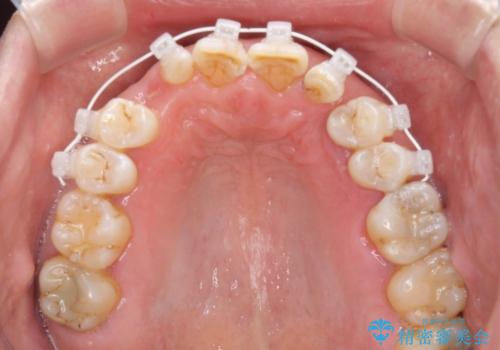

- 矯正装置

- 審美装置

上顎の矮小歯は隙間が多く、歯軸の傾斜も大きかったため、部分矯正により補綴治療前に歯の位置を整えることとしました。

前歯部はディープバイトという、上顎前歯が下顎前歯に深く覆い被さる咬合であったので、理想的には全顎矯正が必要となりますが、今回は患者希望により前歯部のみの部分矯正で対応しました。そのため下顎犬歯の神経を取り除くことになってしまったのは心残りであります。